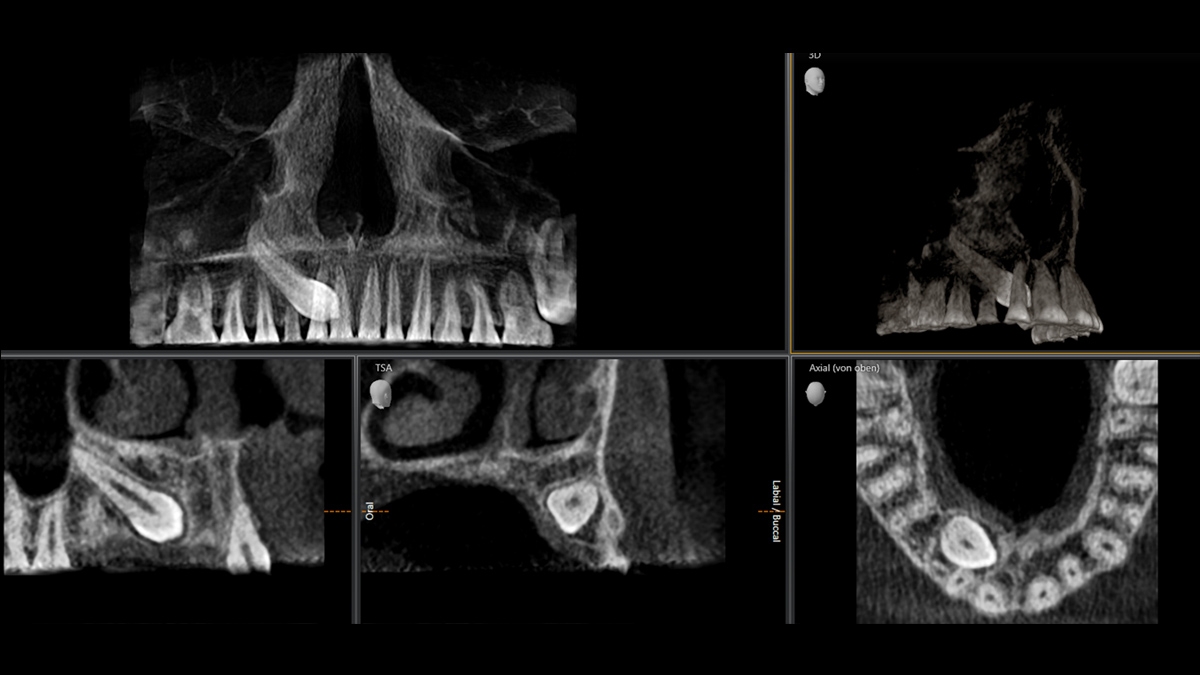

MARS——金属伪影消除软件

金属伪影是3D X射线成像的一大挑战。在三维重建过程中,不透射线的物体会产生阴影和拖尾效应,从而干扰检查结果。MARS自动减少金属伪影,方便诊断。